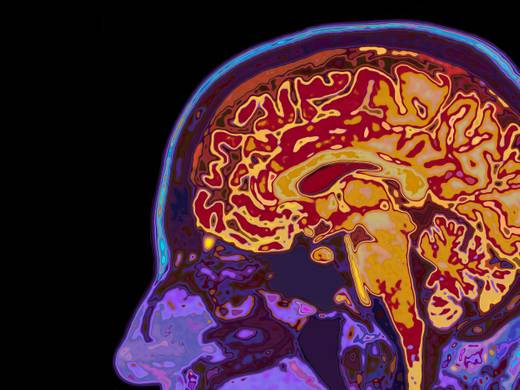

Postgraduate Certificate in Magnetic Resonance Imaging

This will support the development of MRI services within your department and equip you with skills and knowledge to evidence your role as an advanced practitioner in Magnetic Resonance Imaging.